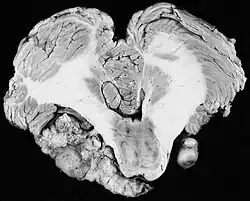

Bilateral schwannomas in a patient with neurofibromatosis type II

For the most part, unilateral sporadic vestibular schwannomas are readily treated successfully by modern medical techniques. Having bilateral VSs is a more troublesome condition. Bilateralism is considered to be the hallmark and main diagnostic criterion of Neurofibromatosis Type II (NF2), a genetic disorder that is heritable, progressive, difficult to manage, and has a 1 in 2 chance of being passed on to each offspring. NF2 patients tend to have a more severe mutation, although there are mild mosaic cases in which only some cells carry the mutation. Genetic testing confirming mutation of the NF2 gene is recommended. About 50% of people with NF2 have a de novo mutation, and about 50% of these new mutations will be mild mosaic cases which are less likely to be passed on. NF2 patients may develop other cranial and spine tumors. NF2 develops during the teens or early adulthood, whereas sporadic VSs are diagnosed mostly in patients between the ages of 40–60 years. Both varieties of VS (sporadic and NF2) are very rare, accounting for only about 8% of all primary brain tumors. The incidence of NF2 is approximately 1 per 60,000 people.[6][7][8]